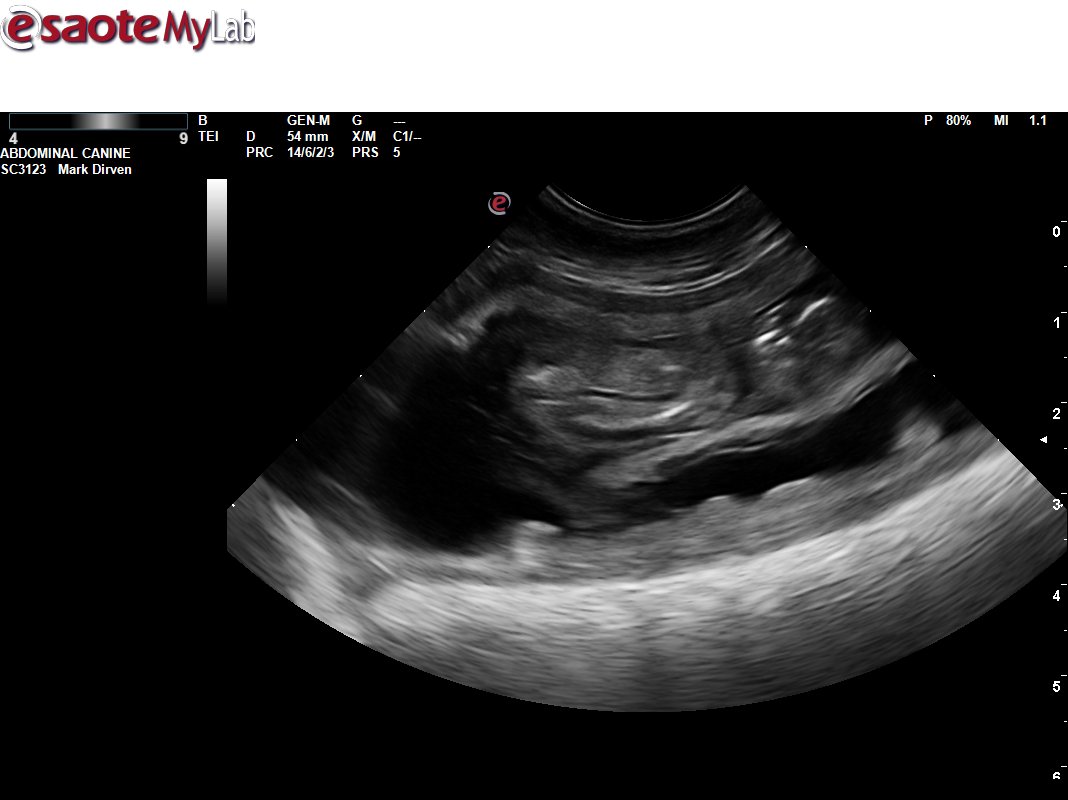

Uitslag heupen Mayla

Mayla 4 september 2019 heupen HD A